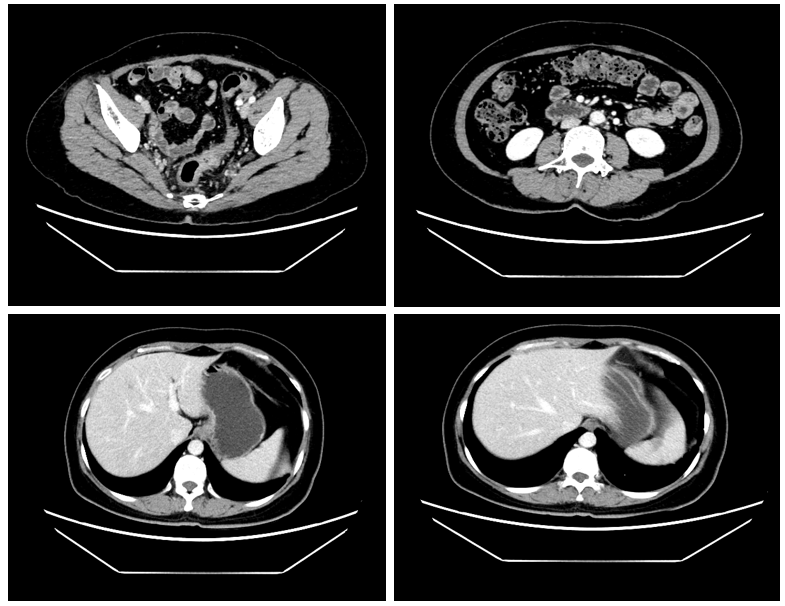

患者于2021年6月及8月分次对肝转移灶行微波消融术;并于2021年7月7日至2021年8月11日予以FOLFOXIRI治疗2周期;于2021年9月7日至2021年12月8日予“卡培他滨+贝伐单抗”方案化疗2周期后暂停贝伐珠单抗同步拟行原发灶切除术,同期继续予以卡培他滨治疗。2、4周期化疗后复查评估病情维持PR(图1)。